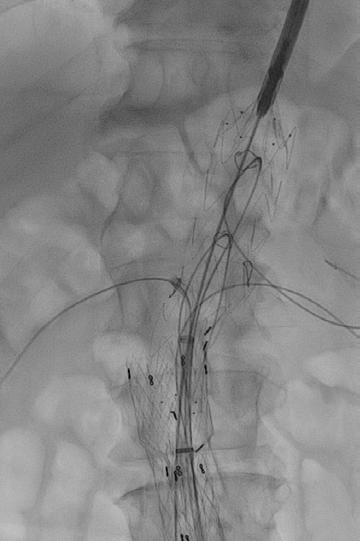

This custom endovascular device can be implanted inside the aorta to seal the aneurysm. A precise opening in the mid segment of the graft allows for blood flow into important arteries while still sealing the aorta above and below the aneurysm.

Below, the graft has been implanted with cannulation of each of the openings and wires placed into each important kidney and bowel artery to maintain blood flow.

Finally, this image shows the sealed aneurysm with continued blood flow in the visceral (kidney and intestinal) arteries.